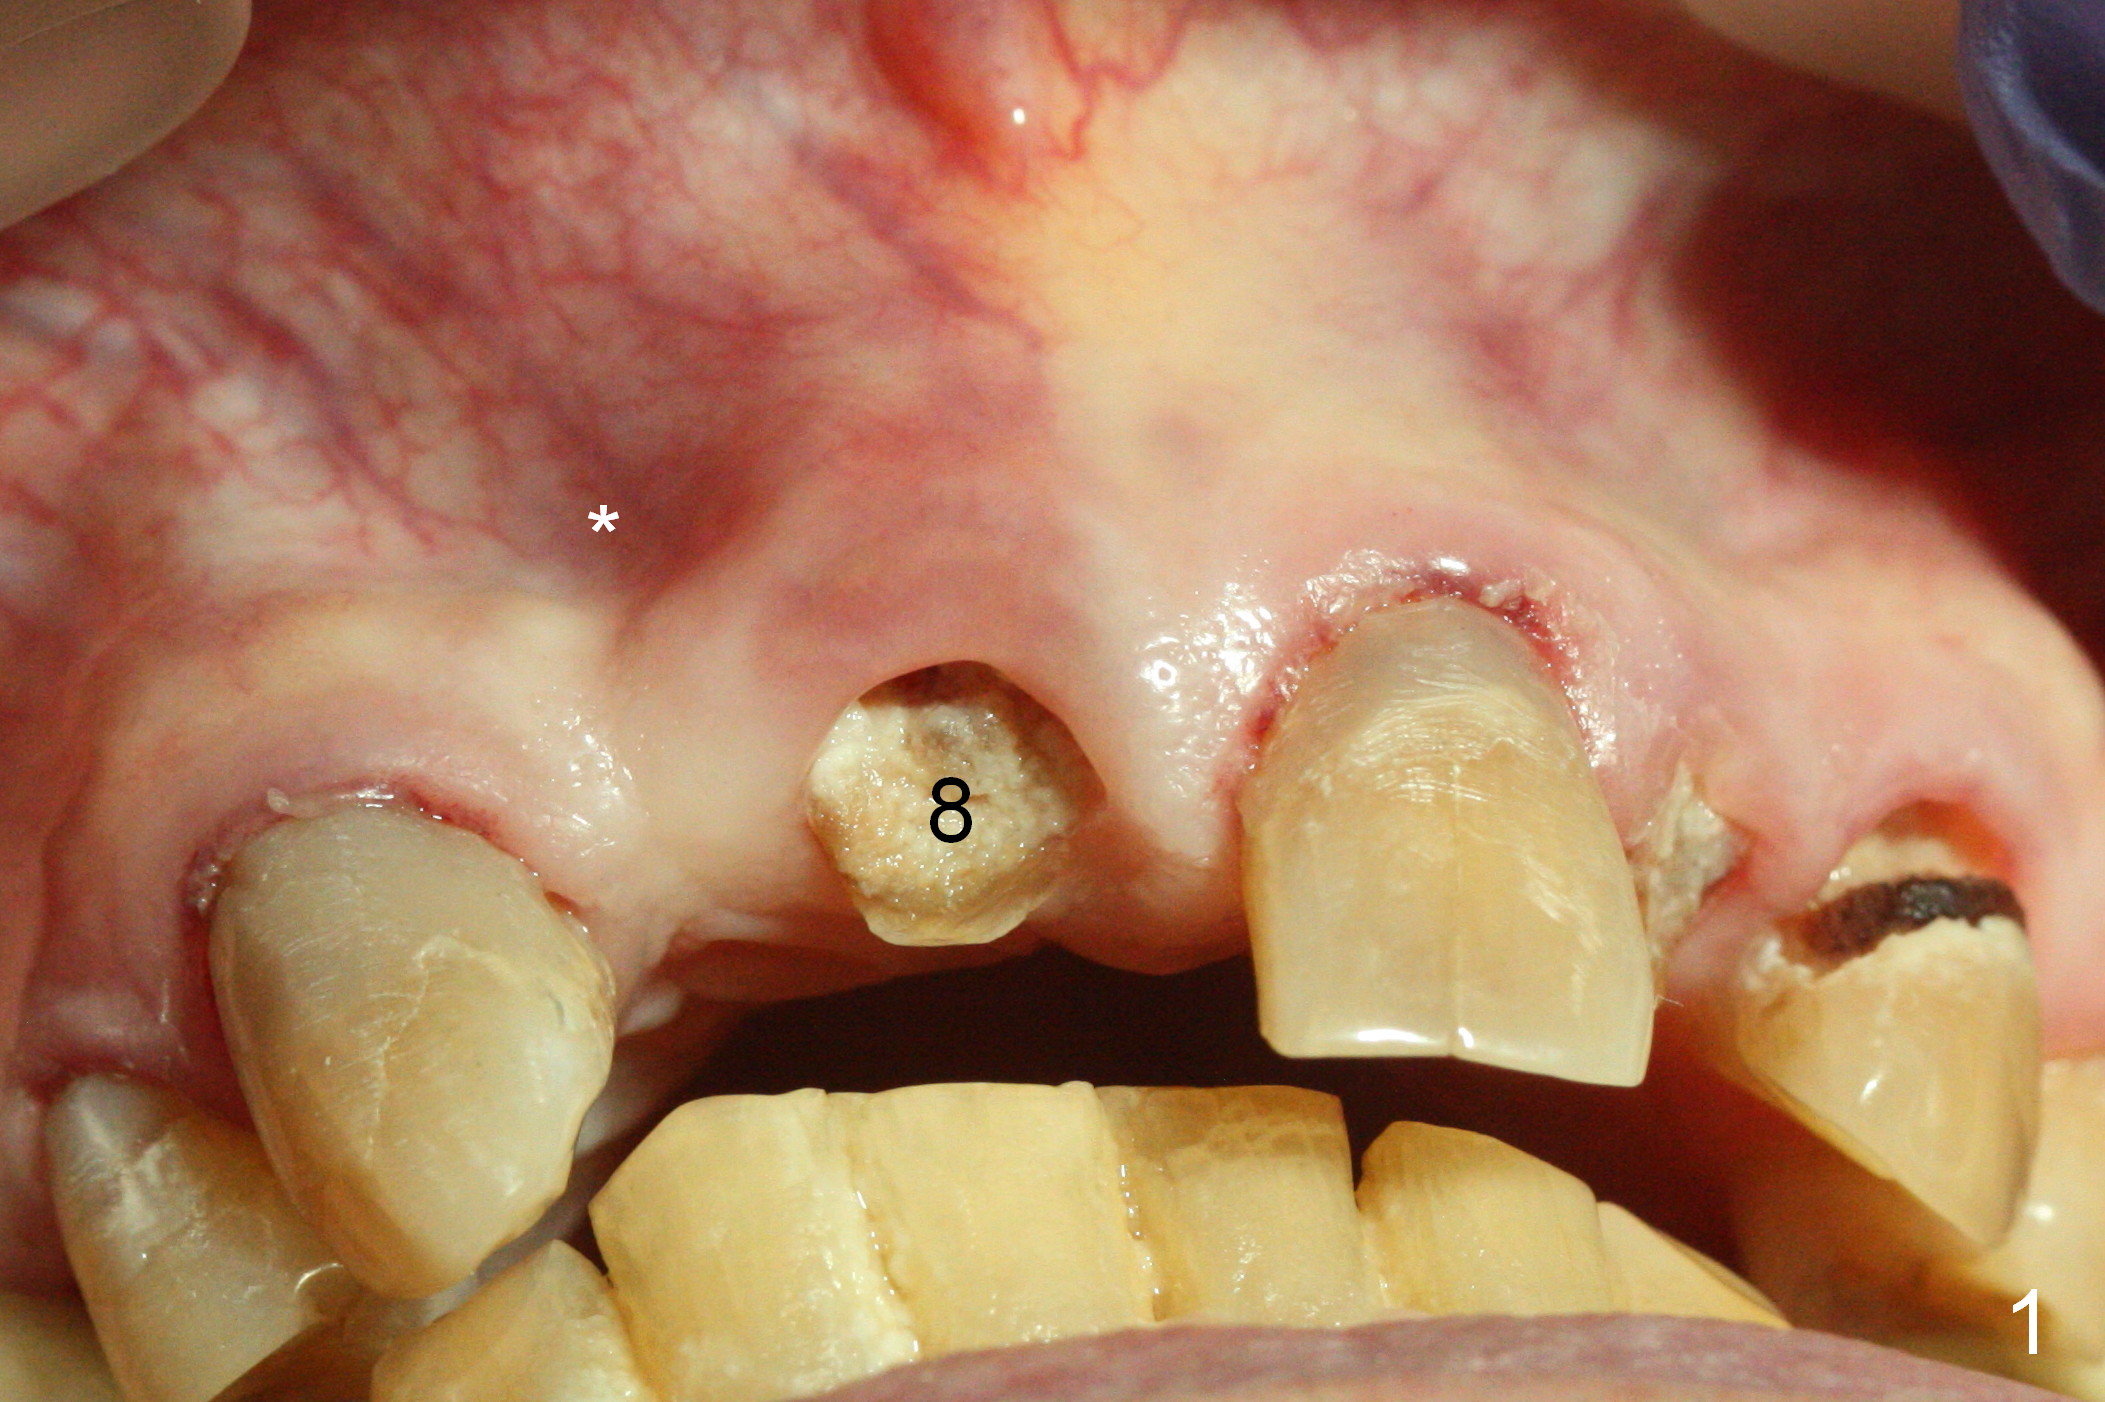

A 88-year-old man (CA) has severe xerostomia-induced caries. After caries control, implants will be placed at #7, 8 and 10 with narrow mesiodistal width (Fig.1,2). Note concavity at the apical buccal plate (*). To prevent perforation, an angled 1-piece implant will be used at #7. Try to place the implant in the middle of the alveolus (digital palpation while drilling) and let the angled abutment take care of the trajectory. To preserve papillae, flapless approach is going to be adopted. Initial depth at these sites will be 12,14 and 14 mm, respectively (Fig.3,4). Use Boley gauge to measure widths of the root to determine the diameter of the implant.